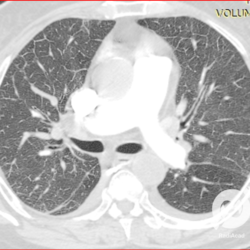

Lesões intersticiais reticulares difusas, aumento do volume cardíaco e inversão da circulação pulmonar (Rx)/ opacidades em vidro fosco e estruturas venosas calibrosas (TC).

Lesões intersticiais reticulares difusas, cardiomegalia, derrame pleural á direita (Rx)/Opacidades em vidro fosco, cardiomegalia e aumento do calibre das estruturas venosas.